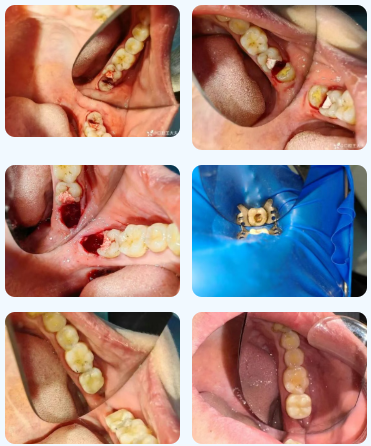

36岁的邹女士深受牙痛困扰,彻夜难眠,遂来到青岛西海岸新区中医医院口腔科就诊。经过详细的口腔检查,发现左下智齿倾斜生长,顶坏了左下第二磨牙,导致牙神经受损,出现冷热刺激痛、夜间痛等。完善曲面断层片等检查,排除手术禁忌后,运用微创拔牙技术顺利实施左下智牙拔除,左下第二磨牙根管治疗+冠修复,为其解决了痛苦。

运用微创器械及微创理念指引下拔牙及根管治疗。

贴心的术后医嘱,让患者更安心及放心。